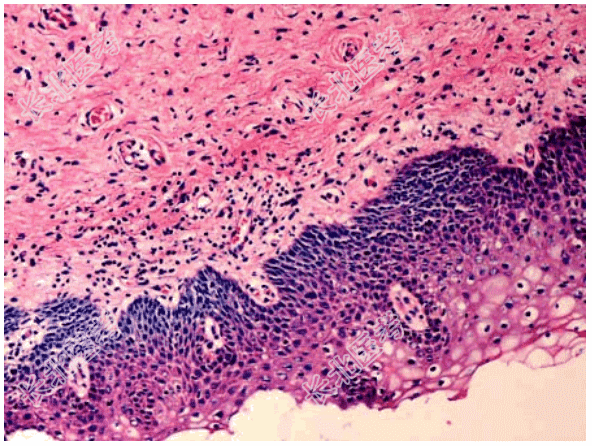

- [材料题] 患者女性,34岁,阴道分泌物增多并有异味,检查宫颈肥大,质硬,宫颈黏膜中度-重度糜烂,取宫颈黏膜活检,显微镜下如图。临床诊断为慢性宫颈炎。

- 简答题1、该疾病的病因包括?

- 简答题2、该疾病的病理改变表现为?